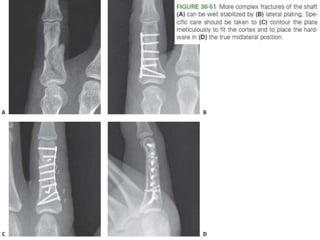

• #84 Figure 30-51 More complex fractures of the shaft can be well stabilized by (B) lateral plating. Specific care should be taken to (C) contour the plate meticulously to fit the cortex and to place the hardware in (D) the true midlateral position.